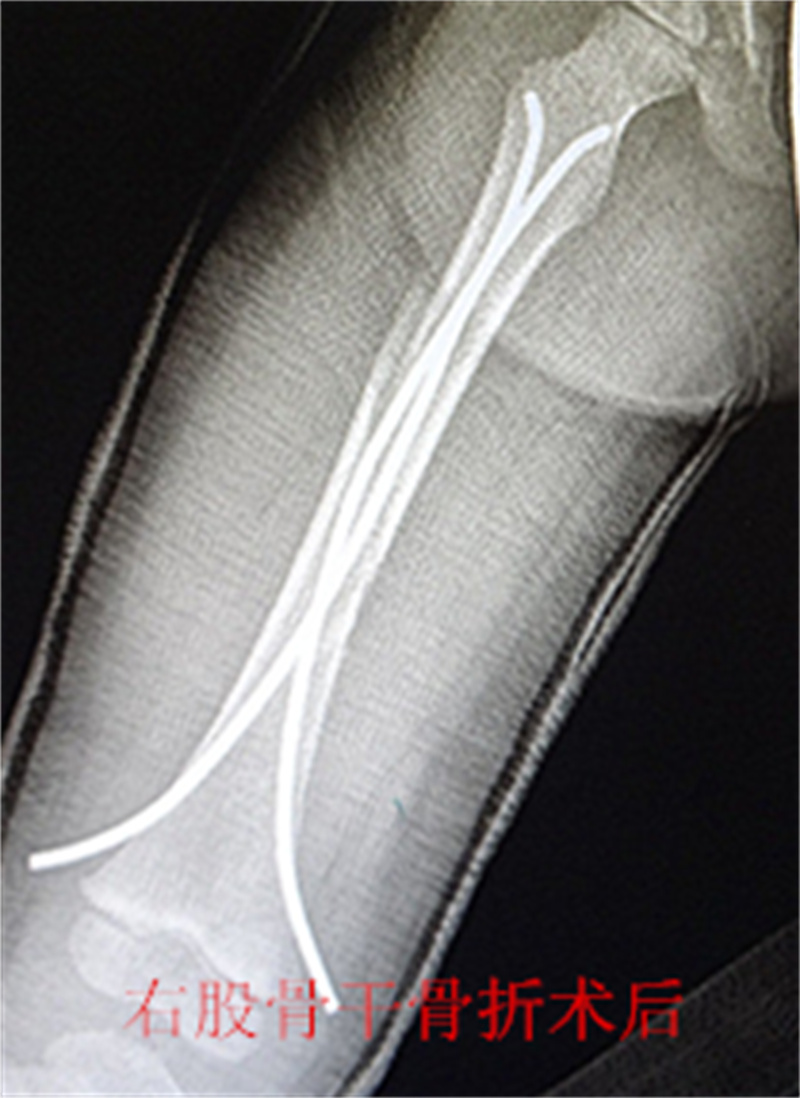

儿童四肢骨折较为常见,保守治疗仍是儿童骨折的重要 治疗方法之一,如牵引,单纯石膏固定等。 往往用时较长,患儿的舒适程度不够,影响患儿及时返回学校学习,这些因素越来越多地影响儿童骨折治疗方法 的选择 。儿童骨折手术治疗的比例较前增加,而传统的手术治疗创伤大,恢复慢,并发症多,如钢板,那是针对成人骨折研发的,用一个坚硬的内固定物固定一个有弹性的骨组织是一个矛盾 ,弹性髓内钉内固定解决了这个矛盾。有人说,弹性髓内钉的出现是上天对儿童的恩惠。的确,弹性髓内钉是治疗小儿长管状骨骨骨折的一种理想、可靠的内固定方法。弹性髓内钉技术发源于法国,在欧洲广泛应用后,现已为全球所接受,被称为是儿童骨科界的一次革命。徐州儿童医院骨一科应用弹性髓内钉技术治疗四肢长管状骨骨折,具有创伤小、恢复快、并发症相对少,孩子能较快恢复正常生活、学习等优点。该技术先将骨折闭合复位,通过微小的切口将特制的弹性髓内钉置入骨髓腔,达到固定骨折的目的。适用于肱骨,股骨,尺桡骨等部位的常见骨折(图)。